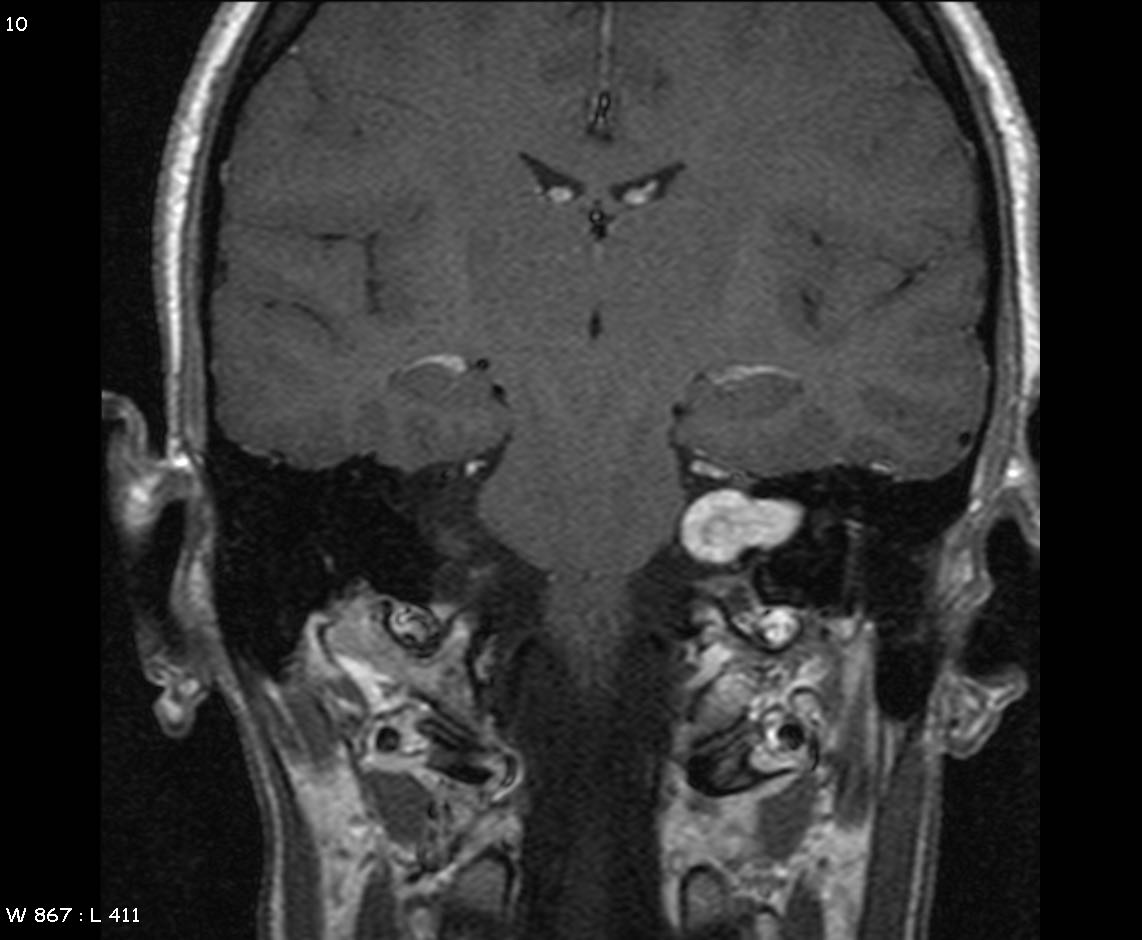

Image

Picture showing MRI scan showing an uncommon brain tumour (acoustic neuroma)- a rare cause of facial nerve palsy